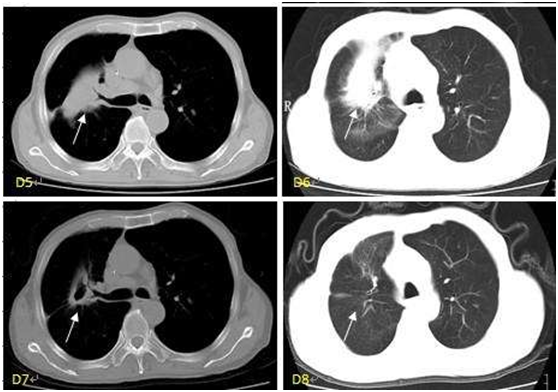

胡主任经过举行国际专家会诊后为我确定了治疗方案,建议采用微创介入联合热疗治疗。这是一趟非常轻松的治疗,并没有我想象中的血腥以及痛苦,做热疗最大的感觉的就是好热,并没有什么不舒服的地方。一开始我觉得无创或者微创的方法会不会效果比较差。但3个月后的复查真让我和家里人都非常惊喜,肿瘤消失的异常明显,而且平时都跟正常人差不多,没有其他的不适。那一刻,我非常欣喜,我的选择是正确的。感谢哥哥的推荐,也感谢胡主任及照顾过的张护士、肖护士等等的努力奉献与悉心照顾。

(杨小姐的肺癌治疗前后对比)